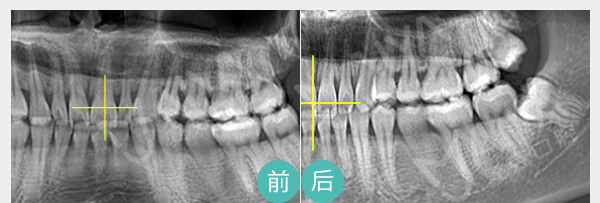

有助于医生判断病情并跟踪治疗效果